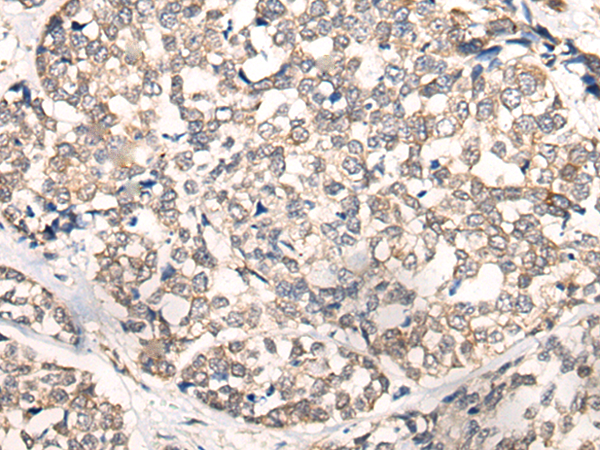

IHC positive control: |

Human liver cancer and human esophagus cancer |

IHC Recommend dilution: |

20-100 |